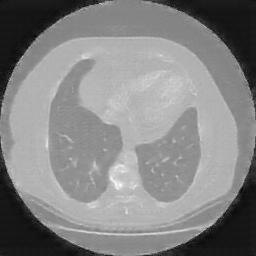

Original VENOUS CT scan

No window - Raw intensity values

Lung window (WL -600, WW 1500 β†’ Low βˆ’1350, High +150)

Mediastinum window (WL 40, WW 400 β†’ Low βˆ’160, High +240)